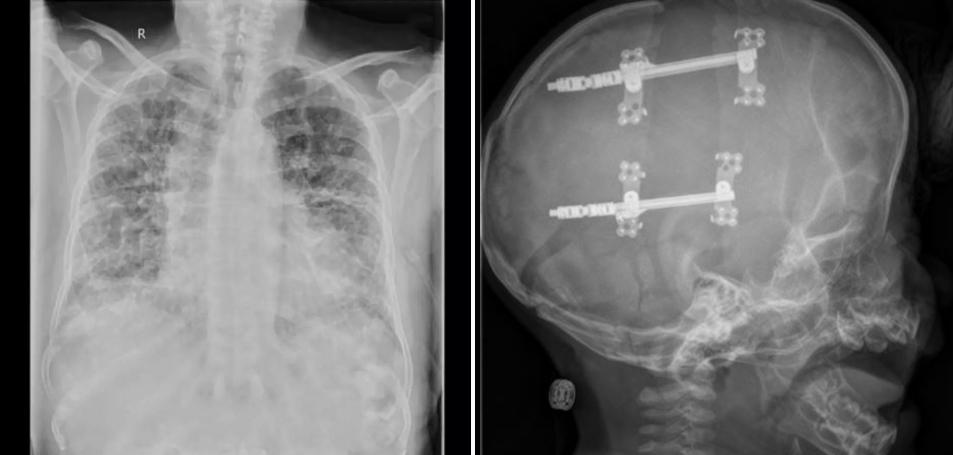

স্ট্রোক চিকিৎসা ও ব্যবস্থাপনা

মস্তিষ্কের রক্তক্ষরণ বা রক্তনালীতে ব্লকেজের কারণে সৃষ্ট স্ট্রোকের দ্রুত ও অত্যাধুনিক চিকিৎসা প্রদান করা হয়। দীর্ঘমেয়াদী ফলো-আপের মাধ্যমে প্যারালাইসিস থেকে রোগীর দ্রুত সুস্থতা নিশ্চিত করা হয় ….. আরও পড়ুন